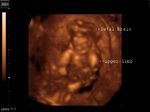

Aneurysm of Vein of Galen

Ultrasound images of intracranial venous aneurysm in fetus:

These are ultrasound images of a 30 week old fetus. Sonography of the fetal brain reveals an anechoic (cystic) lesion posterior to the thalamus and the midbrain. Color doppler image reveals significant flow within this lesion. These ultrasound images are diagnostic of aneurysm of the Vein of Galen. Vein of Galen aneurysms are usually diagnosed in the 3rd trimester. They are usually produced by draining of multiple arteriovenous malformations in the adjacent part of the fetal brain. Differential diagnosis of such lesions includes arachnoid cysts, porencephalic cysts choroid plexus cysts and choroid plexus papilloma (easily diagnosed using color doppler imaging). Choroid papillomas are solid lesions unlike the cystic nature of a vein of Galen aneurymsmal malformation. The other cystic lesions mentioned above would not show flow signal within the lesion on color or Power Doppler imaging.